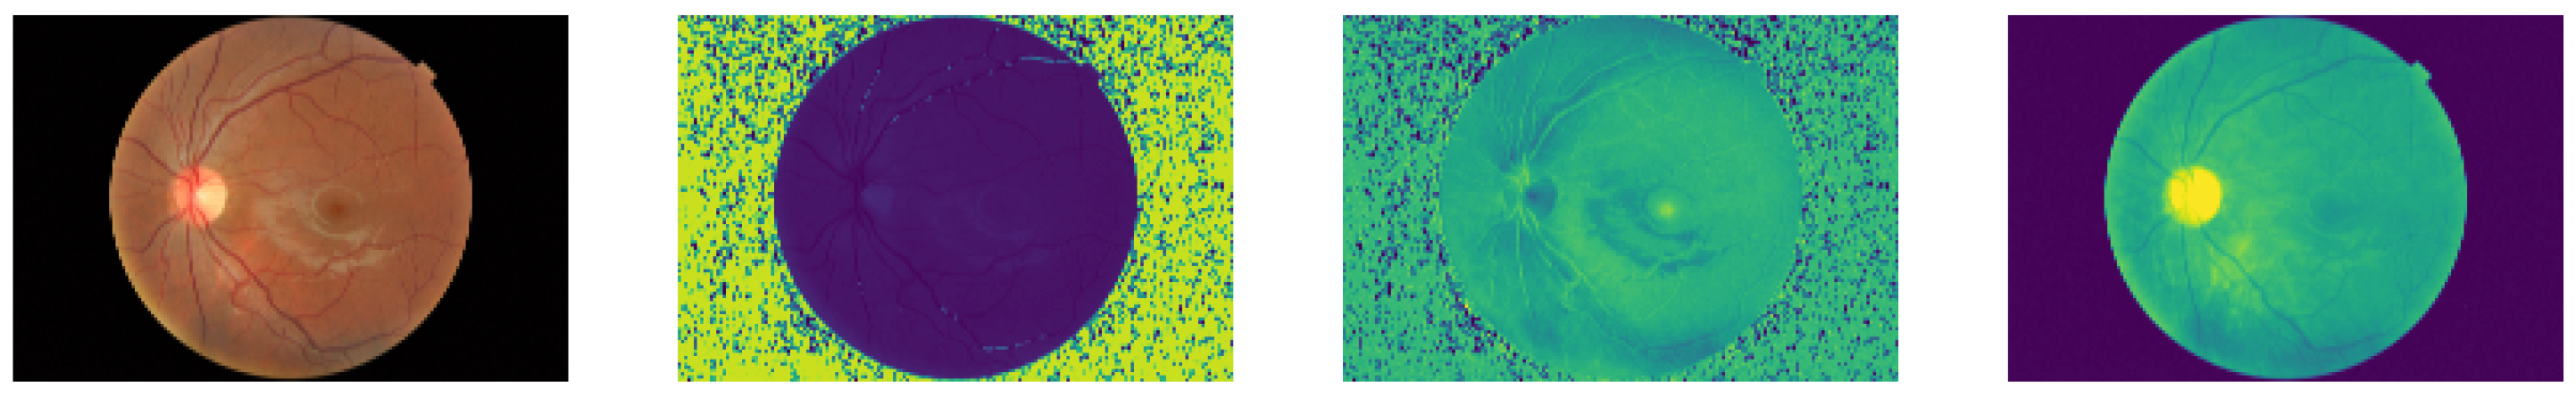

The public RFI databases were generated with different resolutions and compression formats, generating undesirable noise in the image background. For instance, see the HSV representation of an RFI in Figure 2, where speckle noise is present in the saturation and hue channels. As a result, a pre-processing technique based on Briseno et al. [28] is used for background segmentation, automated cropping, and resizing to 224 × 224, preserving their aspect ratios. Figure 3 shows the pre-processing flow diagram in which, given an RFI, the forward pass is performed through the segmentation CNN model (UNet [29]) to obtain a binary mask. After that, generating a bounding box representing the region of interest is possible, which means that everything outside this reference is cropped. Finally, a zero-fill stage is added to maintain a 1:1 aspect ratio.

Figure 2.

Apparently good quality RFI and its three channels in HSV color space. The background noise can be seen, which is mostly associated with image compression.